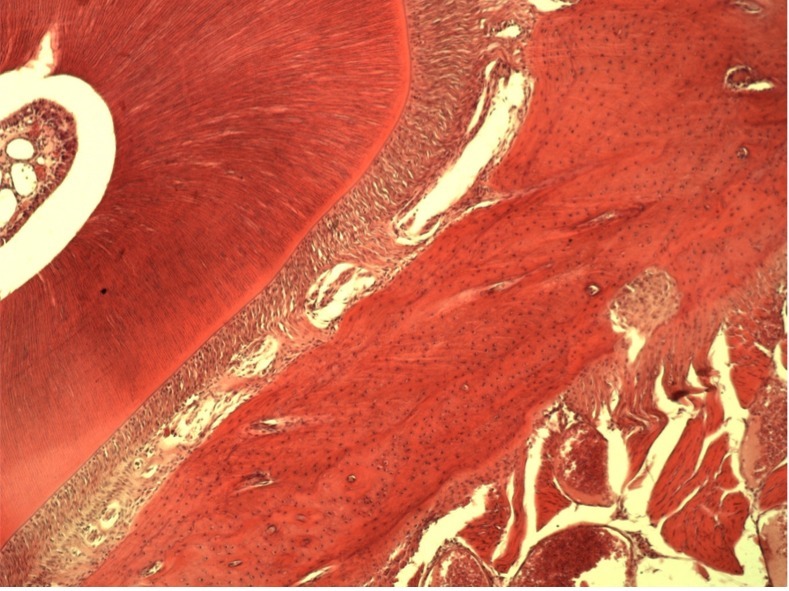

• Например, таким образом удаляются все следы жира, белка, нуклеиновых кислот, мертвых клеток и их компонентов, неколлагеновых белков и прочих соединений. Вследствие такой очистки остается только коллагено-минеральный каркас мертвого межклеточного вещества костной ткани, состав которого стабилен на протяжении всей жизни человека.